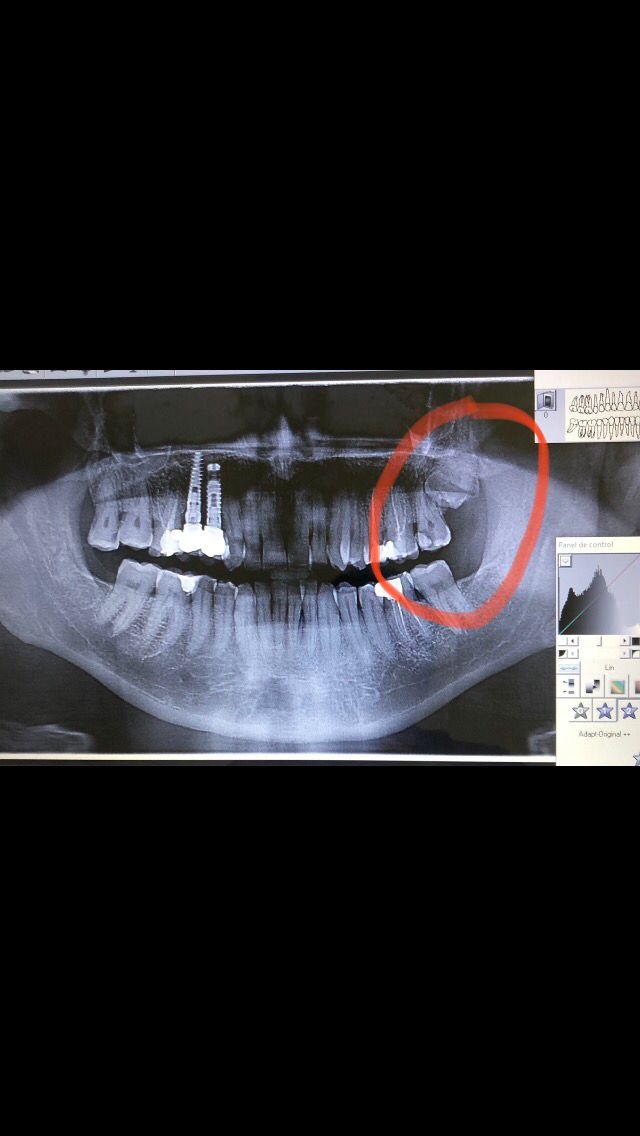

RIZÓLISIS PRODUCIDA POR CORDAL SUPERIOR

Llega un paciente a nuestra clínica con un gran dolor en la zona superior posterior izquierda, concretamente en las piezas segundo molar (27) y muela del juicio (cordal) incluida. A la exploración el paciente presenta una caries en 27 y vemos en la radiografía que a su vez este molar tiene impactado en sus raíces el cordal superior. Le damos tratamiento médico para el dolor e infección que presentaba y le damos cita para hacer la primera parte de la endodoncia en el molar y la extracción del cordal superior. El día de la cita hicimos la primera de endodoncia y la extracción del cordal superior tal y como estaba planificado, la cual fue muy traumática y así terminamos esta primera cita.

Al cabo de tres semanas con el paciente recuperado realizamos la segunda parte de la endodoncia: al hacer la conductometría vemos que la raíz distal vestibular sufrió una rizólisis por el impacto con el cordal. La rizólisis es una destrucción de la raíz de la pieza dental por impacto o presión de la cara oclusal de otra pieza.